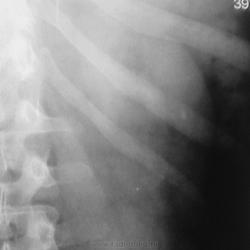

левой почки на уровне 11 12 рёбер определяются тени конкрементов размером до 5-7мм с неровными контурами. Видимо камни в левой почке в её ЧЛС.

После введения контраста.